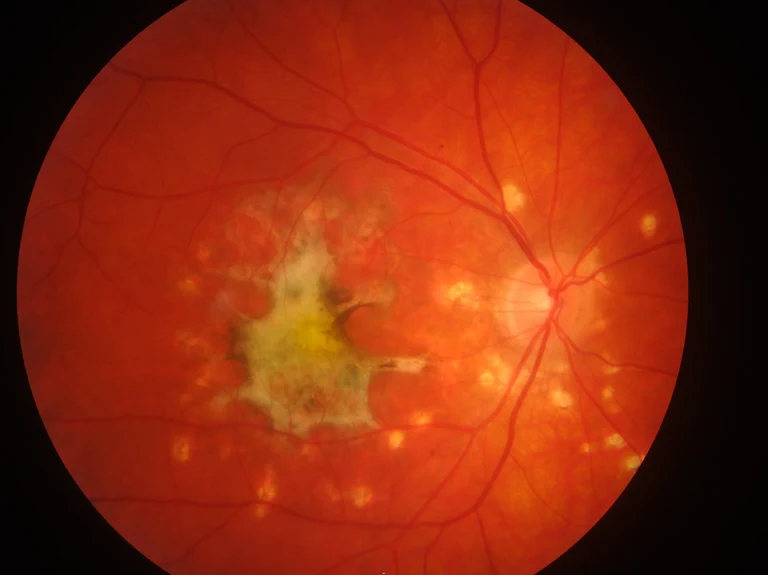

Foto des hinteren Augenabschnittes eines Patienten mit chronischer Entzündung der Aderhaut:

Die große, unregelmäßig begrenzte Läsion in der linken Hälfte des Bilds ist eine große Narbe, daneben kleine Narben im Bereich der Netz- und Gefäßhaut, die alle durch die Uveitis entstanden sind.